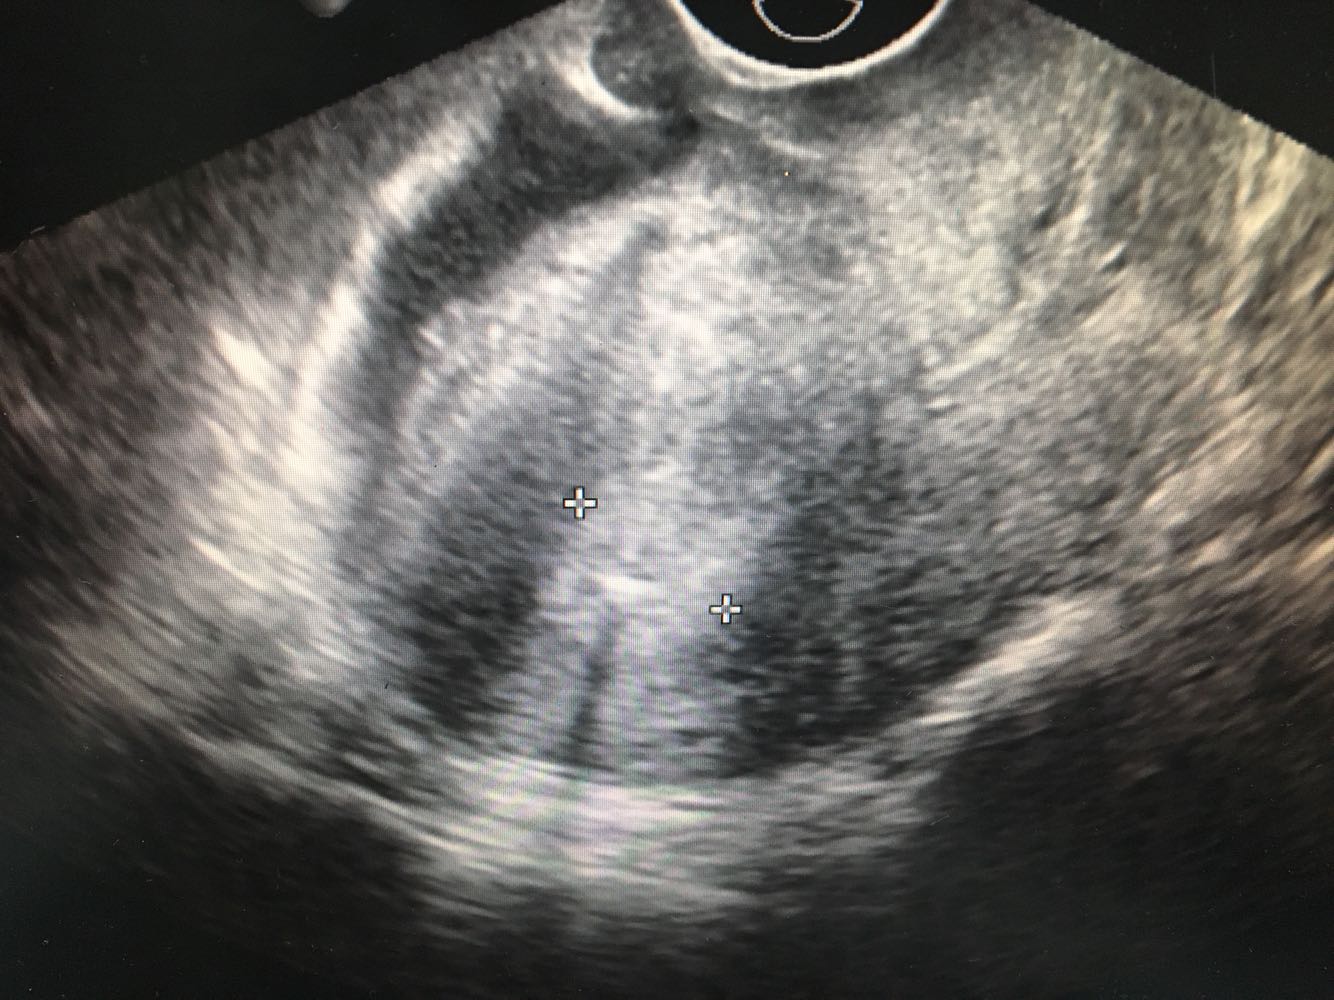

体检:神清,精神可,皮肤巩膜无黄染,轻度贫血貌,浅表巴结未及肿大,颈软,气管居中,双肺呼吸音清,未闻及干湿罗音,律齐,无杂音,腹平软,无压痛反跳痛,未触及明显肿块,肝肾叩击痛(-),移浊(-),NS(-)。        妇科检查:外阴:已婚已产式,阴道:畅,粘膜光,穹窿四周软,宫颈:增大约4cm,表面糜烂增生状,可见异型血管,触血(+)附件:未及明显异常,三合诊:双侧宫旁未及增厚。 5.辅助检查:【宫颈TCT】示不能排除高度鳞状细胞病变的非典型鳞状细胞癌(ASC-H)  【宫颈活检病理】示非角化型鳞状细胞癌,部分处浸润生长